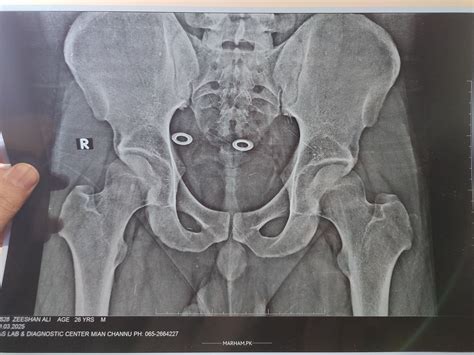

Iliac Crest Muscle Pain